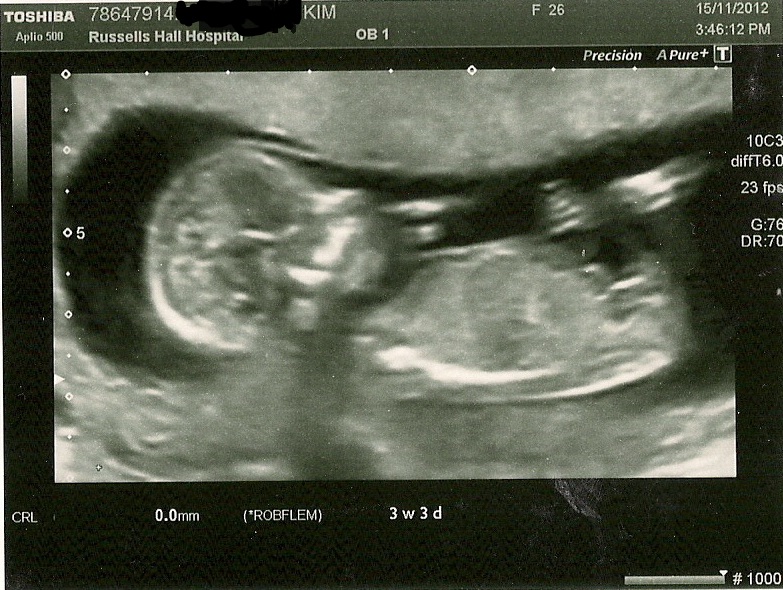

This was my 12 weeks scan, when i went my baby measured at 13 weeks exact. Could you please take a guess and tell me if im having a prince or princess??Attachment 6425

Only part of the nub is visible so I'm 50/50.

end of nub is not visible slight boy lean

Maybe girl

Leaning girl...GL!